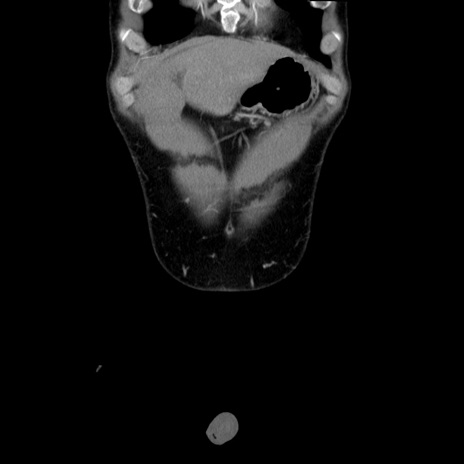

横断像

【症例】20歳代 男性

【主訴】心窩部痛

【現病歴】今朝より上腹部痛あり。一旦軽快していたが再度出現したため救急要請。昨日夕に白身の魚を含む刺身を食べた。

【身体所見】BP 136/89mmHg、HR 74/min、BT 37.0℃、腹部:膨満、軟、心窩部に圧痛あり。反跳痛なし、筋性防御なし、腸雑音やや亢進あり。

【データ】WBC 17700、CRP 0.48